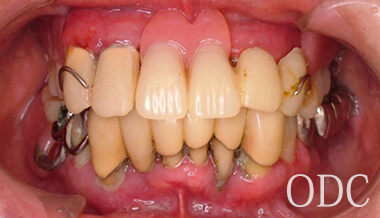

術 前

術前

初診時87歳、男性。上顎は歯周病により残存歯を長期的に機能させることが困難と判断し、全て抜歯。出来る限り早期の咬合機能の回復と審美性の実現が求められ、上顎は「4本のインプラントで失った全ての歯を固定し、手術当日から噛む機能を回復させることが可能」なオールオン4という術式を選択。オールオン4は「治療期間」「経済性」「審美性」「外科的侵襲」などのあらゆる負担を軽減した全く新しいコンセプトの画期的なインプラント治療です。 下顎の欠損部位に対しても、術前の診査診断をしっかり行い合計5本のインプラントを埋入しました。

インプラント治療を成功に導く為に必要不可欠な歯科技工。インプラント補綴は、特に技工士の技術が重要となる。オールオン4において、“口の中の見える部分”は全て歯科技工士の仕事なのです。当医院のオールオン4補綴はインプラント補綴で有名なノーベルバイオケア社公認インストラクター 志田和浩氏によるものです。本症例は、1歯1歯プロセラを装着した、オールオン4の上部構造としては最高級のものの一つです。